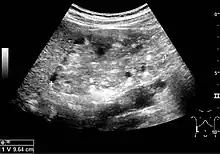

Complex cysts can have membranes dividing the fluid-filled center with internal echoes, calcifications or irregular thickened walls. The complex cyst can be further evaluated with Doppler US, and for Bosniak classification and follow-up of complex cysts, either contrast-enhanced ultrasound (CEUS) or contrast CT is used (Figure 6). The Bosniak classification is divided into four groups going from I, corresponding to a simple cyst, to IV, corresponding to a cyst with solid parts and an 85–100% risk of malignancy.[1] In polycystic kidney disease, multiple cysts of varying size in close contact with each other are seen filling virtually the entire renal region. In advanced stages of this disease, the kidneys are enlarged with a lack of corticomedullary differentiation (Figure 7).[1]

Figure 7. Advanced polycystic kidney disease with multiple cysts.[1]